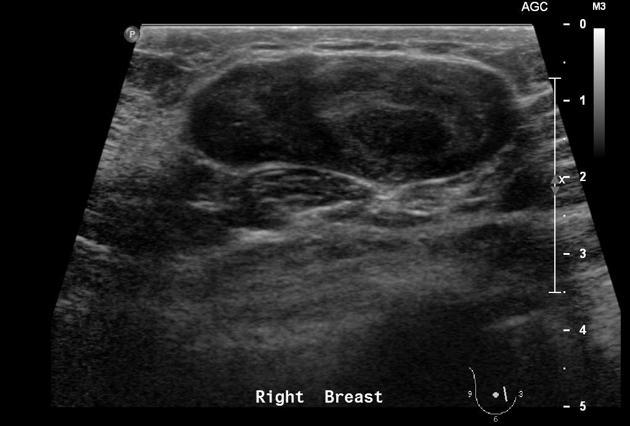

Diagnosis?

Fibroadenoma. By ultrasound, oval or gently lobulated hypo to iso-echoic mass. Parallel orientation.

Oval, round, or macrolobulated. Low/isodense to the breast parenchyma. Can calcify.

(Tubular adenoma would also be on the differential for this US appearance, but higher density on mammo)